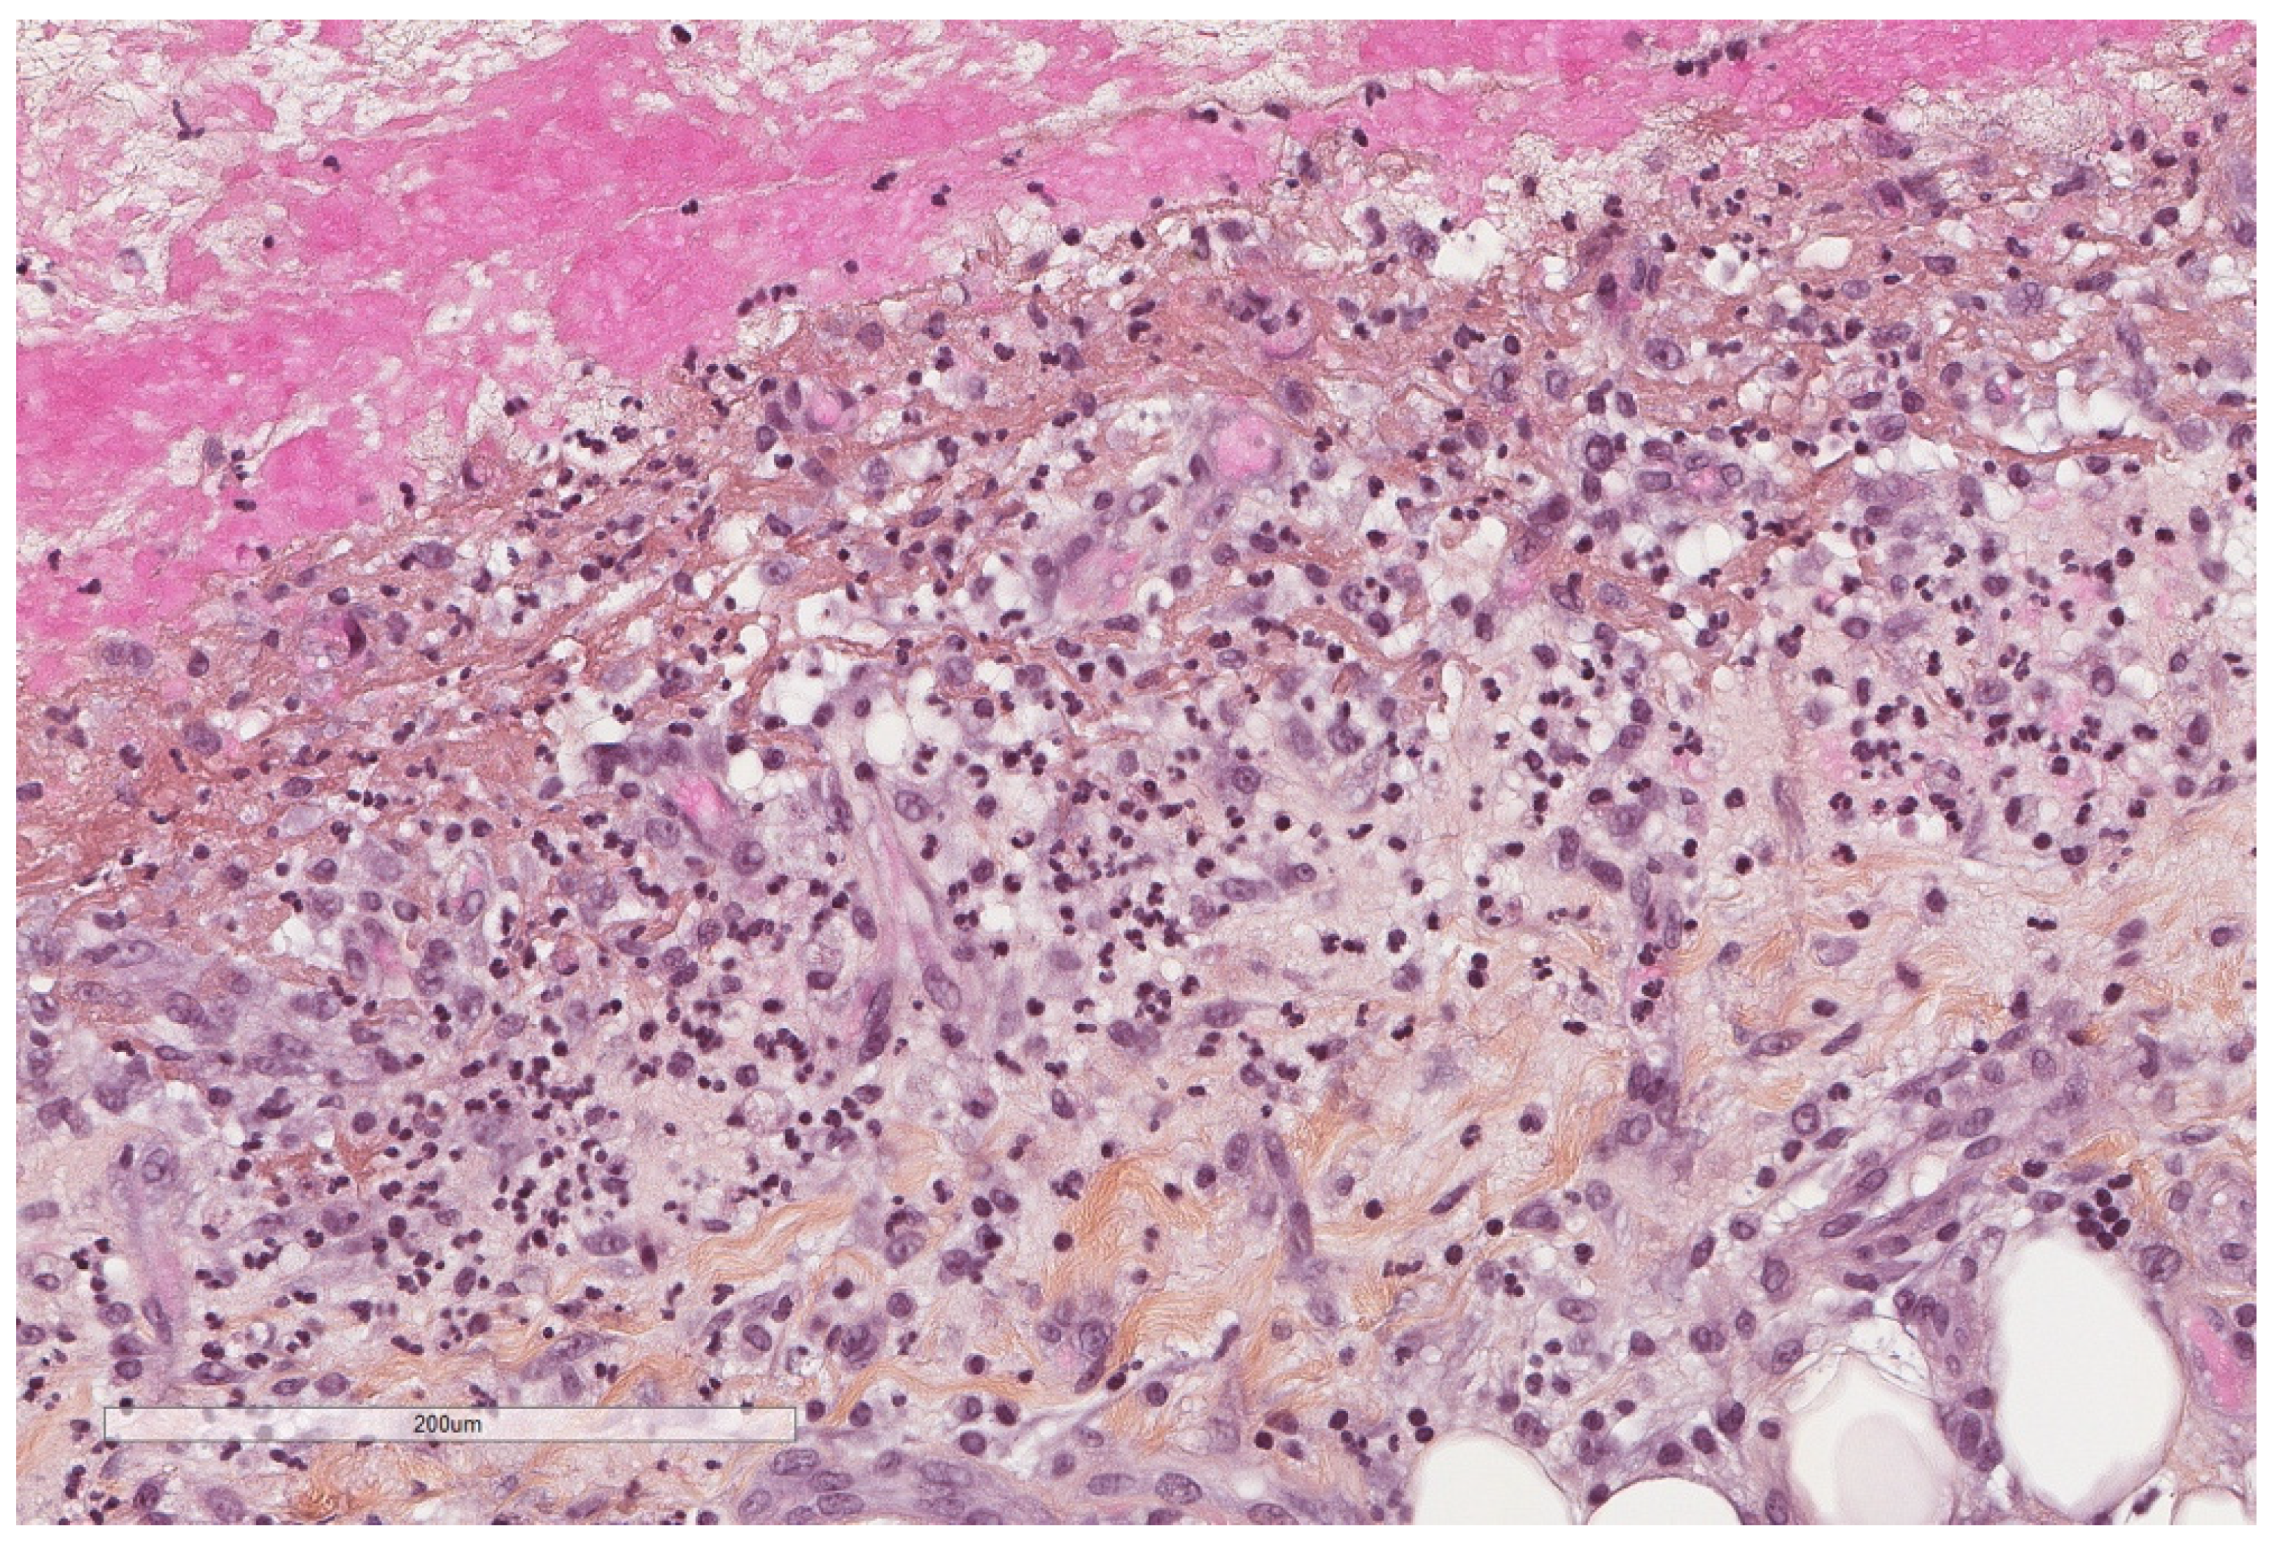

- Karpathiou, G.; Hathroubi, S.; Patoir, A.; Tiffet, O.; Casteillo, F.; Brun, C.; Forest, F.; Rahman, N.M.; Peoc’h, M.; Froudarakis, M.E. Non-specific pleuritis: Pathological patterns in benign pleuritis. Pathology 2019, 51, 405–411. [Google Scholar] [CrossRef] [PubMed]